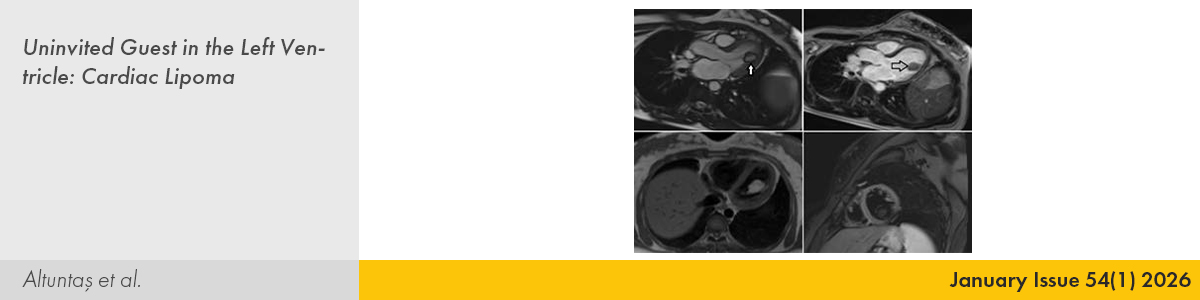

| 10. | Uninvited Guest in the Left Ventricle: Cardiac Lipoma Emine Altuntaş, Kadriye Memiç Sancar, Begüm Uygur, İffet Doğan PMID: 40625269 doi: 10.5543/tkda.2025.35332 Pages 68 - 70 |